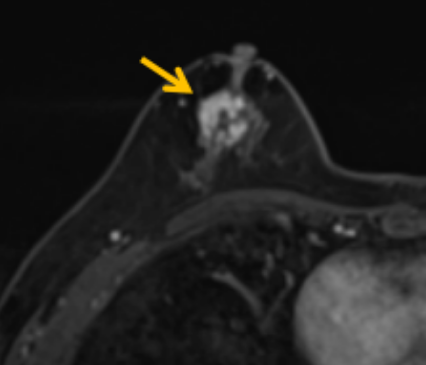

陳寶瑩評估圖像后發(fā)現(xiàn)病變?yōu)閮H僅在磁共振增強時顯示,為非腫塊樣病變,比較散,必須取得足夠多的組織才能確保病理檢查的準確性,常用的核芯針活檢獲取的組織較少,因此最終確定了磁共振引導下行真空輔助抽吸旋切活檢。取得患者及家屬認可后,陳寶瑩帶領(lǐng)團隊開始進行術(shù)前準備。

針對患者乳房小固定難度大這一問題,陳寶瑩通過巧妙體位和固定器的調(diào)整,順利固定好乳房。經(jīng)過磁共振多模態(tài)掃描,陳寶瑩找出病變活性成分相對集中區(qū)域,精準確定穿刺路徑,置入引導針、旋切針,到位后多角度旋切取出足量組織,拔除旋切針后即時行磁共振掃描,精準取得組織且術(shù)區(qū)出血很少,遂加壓包扎,整個過程非常順利,旋切活檢后患者回家休息。兩天后隨訪,李女士沒有任何不適,五天后皮膚上幾毫米的小切口已經(jīng)愈合。最終病理結(jié)果證實為乳腺導管原位癌,為早期乳腺癌,為患者后續(xù)針對性治療奠定了基礎。